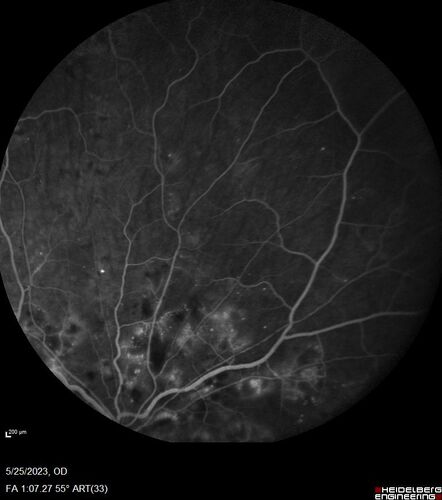

Siegrist Streaks and severe diabetic macular edema

56 year old female who presents four years after developing necrotizing fascitis and multiple organ failure from an infected foot from a roofing nail.  Her vision was 20/100 OU.  She has multiple peripheral pigment spots consistent with Siegrist streaks.